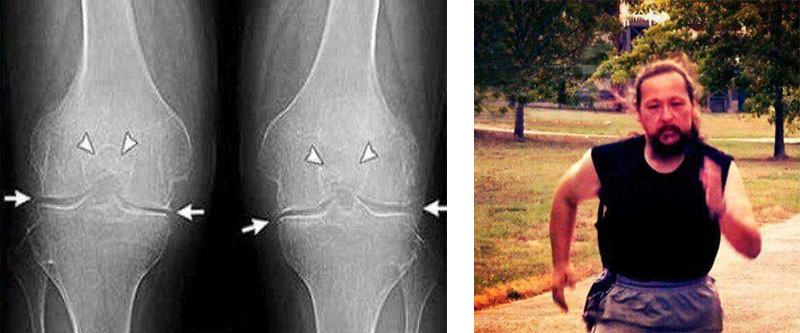

διαφορά:

πόδι μου. Ο πατέρας μου μου έφερε από κάπου το και Artroviv Flex+ Δόξα το Θεό! Δείτε την διαφορά:

Εμένα το Artroviv Flex+ με βοήθησε πολύ! Πρήστηκε το γόνατο δεν μπορούσα να λυγίσω το πόδι μου. Ο πατέρας μου μου έφερε από κάπου το και Artroviv Flex+ Δόξα το Θεό! Δείτε την διαφορά: